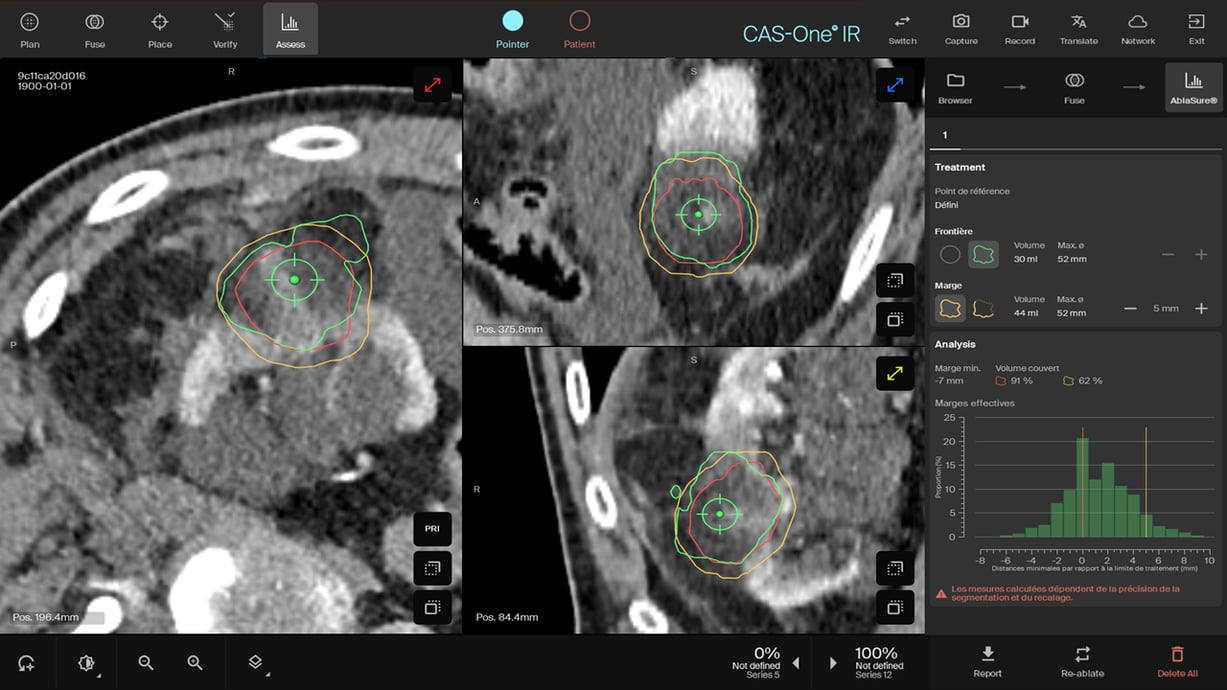

AblaSure confirming full coverage of the tumor post retrieval of the needles

- AblaSure® showed a complete coverage after the 2nd freeze cycle and also confirmed post thawing and retrieval of the needles.